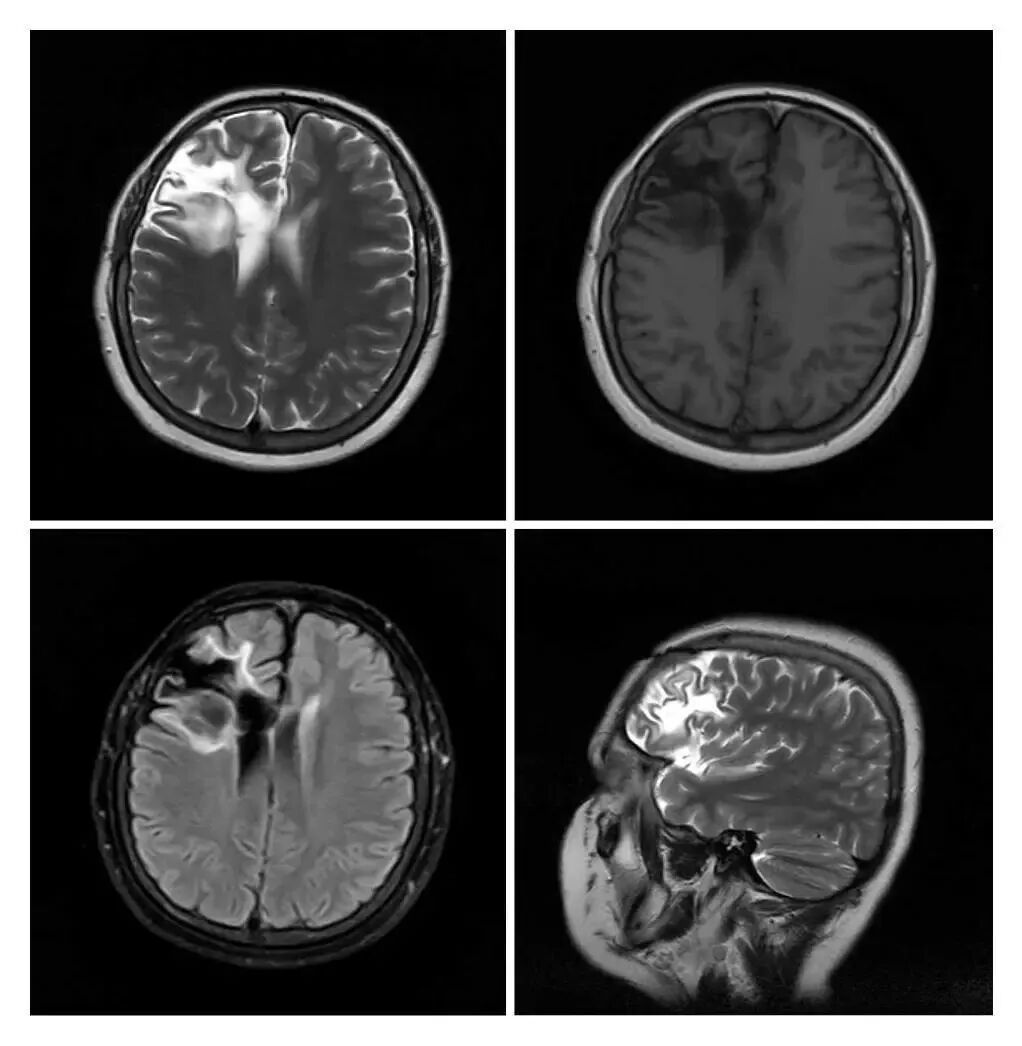

MRI現(xiàn)已應(yīng)用于全身各系統(tǒng)的成像診斷。效果最佳的是顱腦,及其脊髓、心臟大血管、關(guān)節(jié)骨骼、軟組織及盆腔等。而且不同于已有的成像術(shù),它對疾病的診斷具有很大的潛在優(yōu)越性。多序列成像、多種圖像類型,為明確病變性質(zhì)提供更豐富的影像信息,能很好的滿足臨床的診斷需求。

滑動查看更多